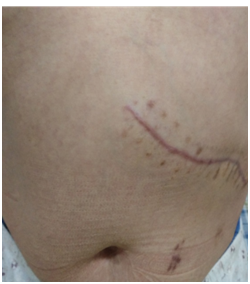

传统的开腹手术需要在腹部切开一个约20—25cm大小的切口,然后进行病灶切除。而腹腔镜手术只需在皮肤表面做3—5个直径约0.5—1cm小孔,腹壁上没有传统开腹手术的大切口,手术创伤小、术后疼痛少、恢复快,故被称为微创手术。

4、腹腔镜手术腹壁戳孔小(直径5—10mm不等),取代了传统腹壁大切口,避免了腹壁肌肉、血管和相应神经的损伤,而且切口隐蔽,愈合后瘢痕小,美容效果好。戳孔感染的发生率明显低于传统开刀手术。

图片

传统开腹手术

腹腔镜微创手术